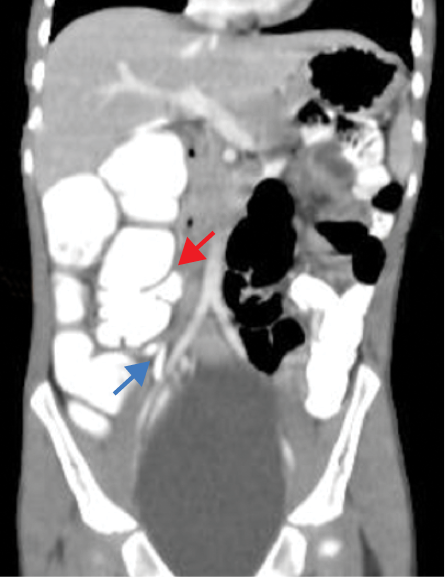

The contrast-enhanced computed tomography (CECT) abdomen findings were as follows: The D3 segment of the duodenum was seen to cross to the left side with the duodeno-jejunal junction in its expected location. The superior mesenteric arter-superior mesenteric vein (SMA-SMV) relationship was maintained with the SMV lying on the right side of SMA. The small bowel loops were predominantly on the left side of the abdomen, and the entire colonic loops were positioned on the right side of the abdomen [Figure 1]. The ileocecal junction (ICJ), cecum, and appendix were noted in the right lumbar region [Figure 2]. The inferior mesenteric artery was seen coursing to the right side of the midline, rather than its normal left-sided course [Figure 3]. A tubular cystic lesion was observed in relation to the small bowel loops on the left side of the abdomen [Figure 4]. Intrabdominal solid organs were essentially normal, with a normal situs.

Figure 1: Coronal sections of the contrast-enhanced computed tomography scan of the abdomen, showing the abnormal positioning of the small bowel loops on the left side (red arrow), and the large bowel loops on the right side (blue arrow), suggesting the possibility of hindgut malrotation.

Figure 2: Coronal sections of contrast-enhanced computed tomography abdomen showing the position of the ileocecal junction (red arrow), cecum and appendix (blue arrow) in the right lumbar region.